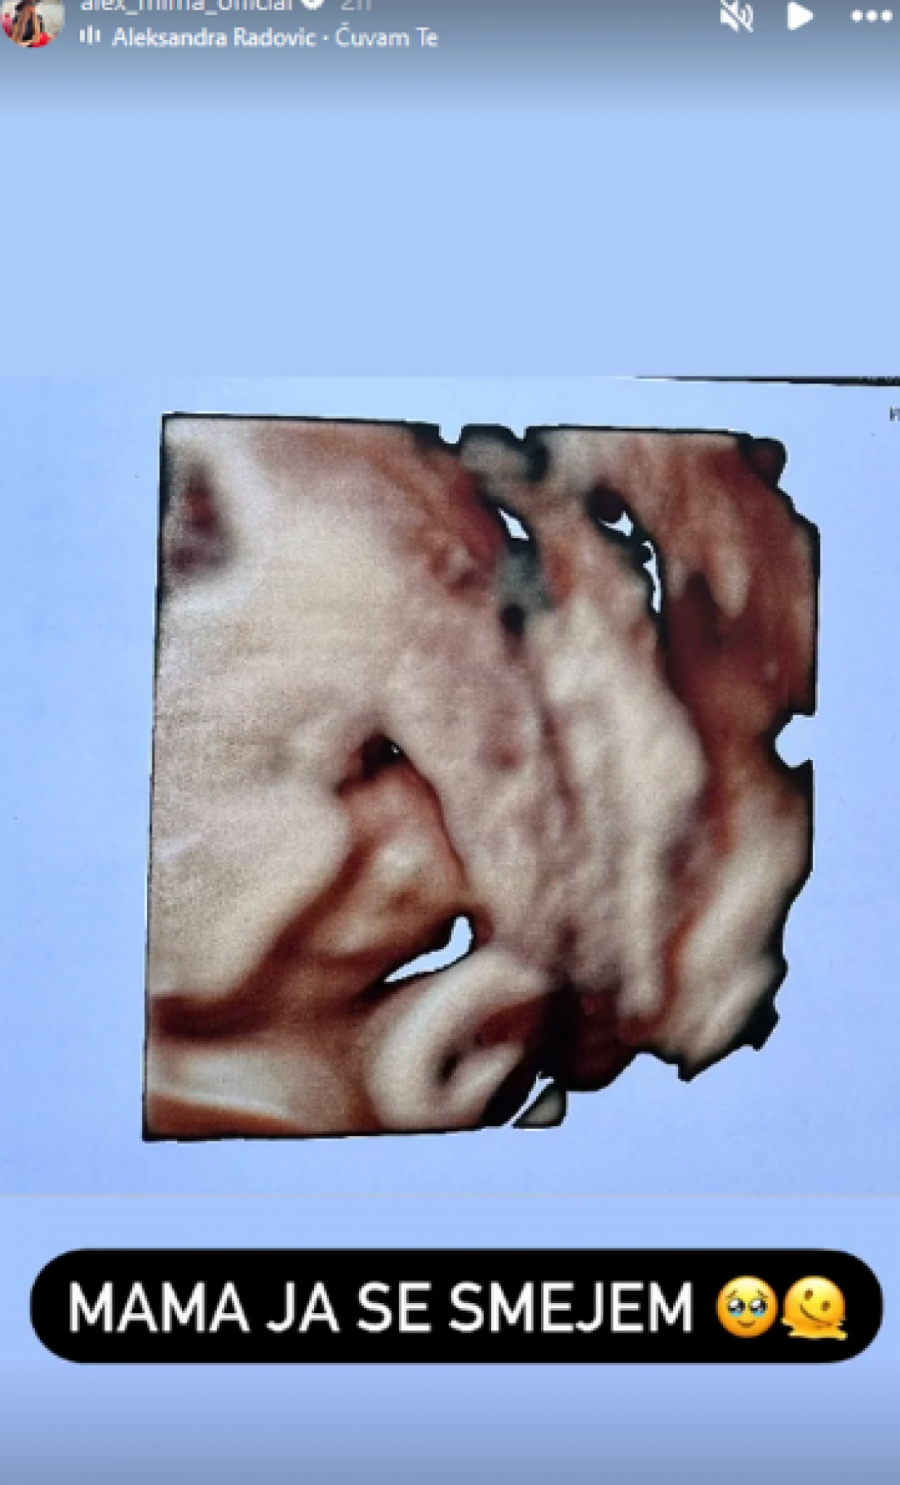

Naime, Aleksandra je na svom Instagram profilu večeras objavila snimak sa ultrazvuka i dodala opis koji nikog nije ostavio ravnodušnim.

- Mama, ja se smejem - napisala je Aleks i dodala emotikon koji plače od sreće i emotikon koji se "topi".